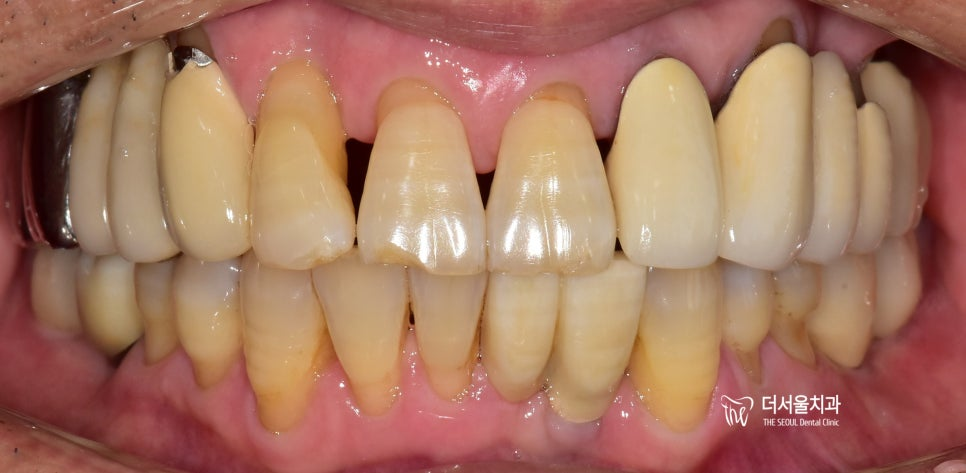

앞니 는 기능적인 측면뿐만 아니라 심미적인 요소도 함께 고려해야 됩니다. 그래서 보철의 형태와 색상 등을 여러 번 체크하고 확인하는